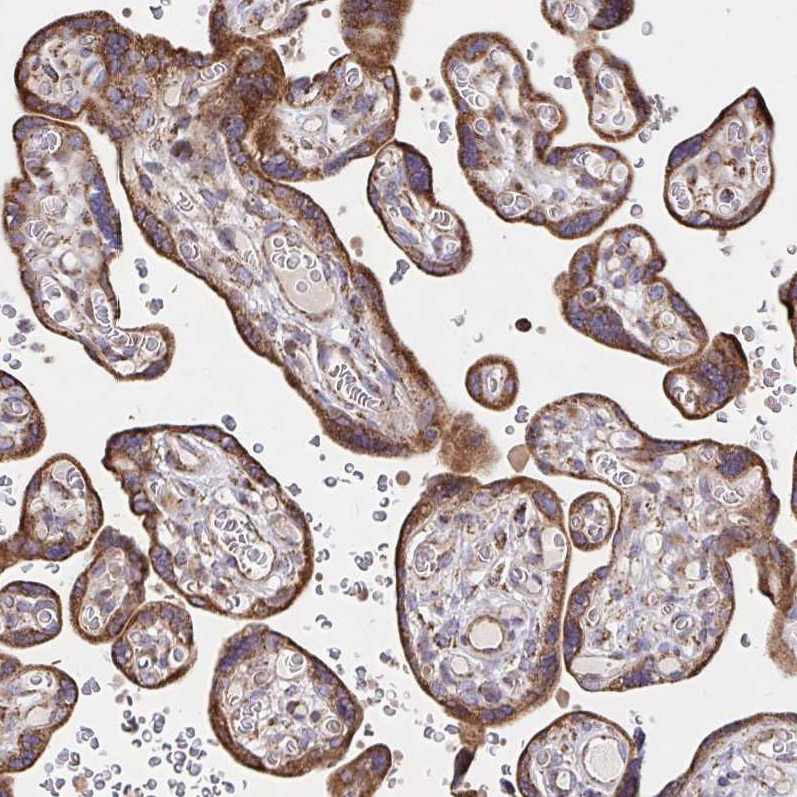

Immunohistochemical staining of human placenta shows strong cytoplasmic positivity in trophoblastic cells.